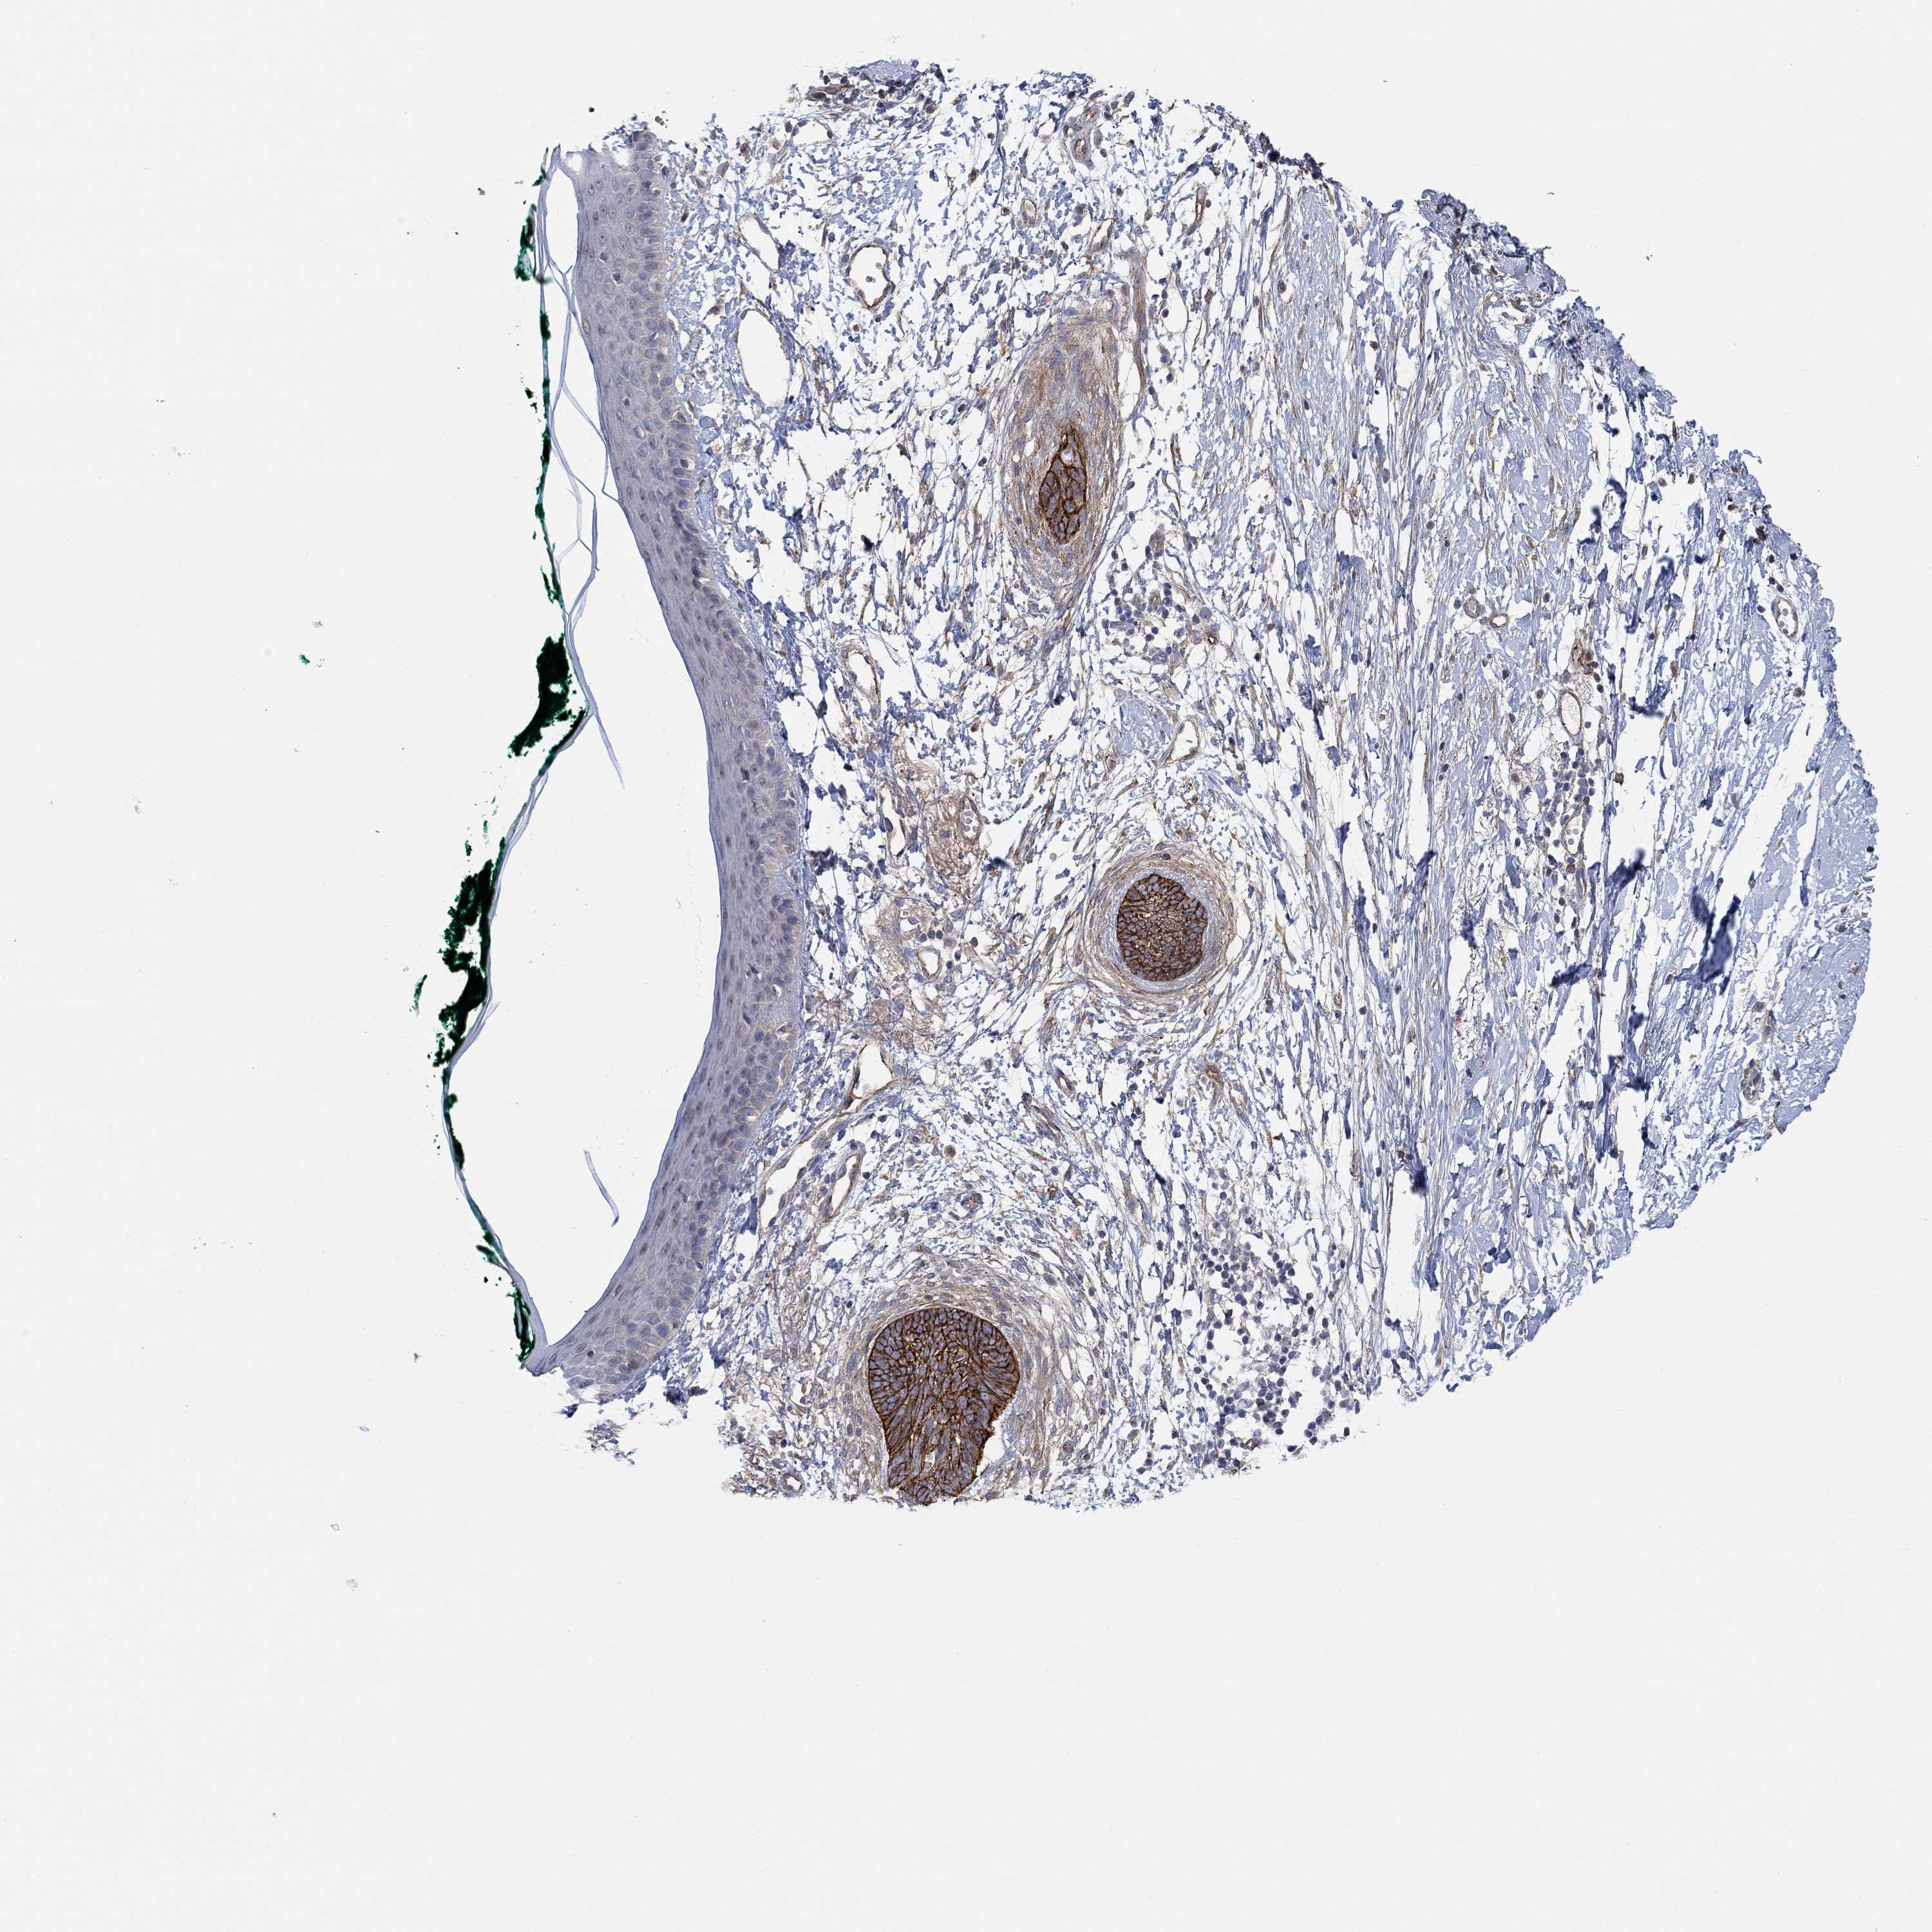

CANCER SKIN CANCER Show tissue menu

Basal cell and squamous cell cancer

Human cancer

SKIN CANCER - Protein expressioni

A mouse-over function shows sample information and annotation data. Click on an image to view it in a full screen mode. Samples can be filtered based on level of antibody staining by selecting one or several of the following categories: high, medium, low and not detected. The assay and annotation is described here.

Each image is clickable and will lead to virtual microscopy that enables deeper exploration of all samples and also displays staining intensity scores, fraction scores and subcellular localization as well as patient and tissue information for each sample.

Antibody HPA004199

Squamous cell carcinoma, NOS

Basal cell carcinoma